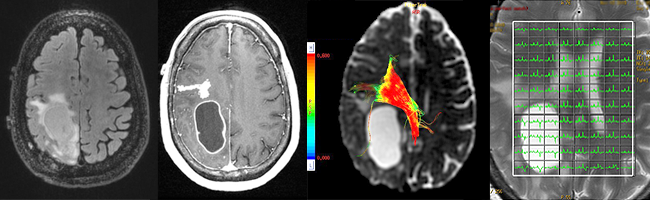

Neuroradiology focuses on imaging and therapies to diagnose and to treat disorders of the adult and pediatric brain, spine, neck, and central and peripheral nervous system. The UCSF neuroradiology group is comprised of internationally recognized experts in every one of these disciplines, and in the latest state-of-the-art imaging with CT, MRI, MEG and molecular modalities such as PET. The group has expertise in the full array of neurologic disease, including brain tumors, stroke and other vascular disorders, spine disease, neurodegenerative diseases, and brain malformations. With 12 full-time neuroradiologists across our campuses, we are one of the largest divisions of neuroradiology in the United States.

Patients are referred to UCSF neuroradiology from all over the world. Each year we perform and interpret over 14,000 CTs, 22,000 MRIs, 250 myelograms, more than 1,000 diagnostic angiograms, over 650 interventional procedures, and more than 500 spinal procedures including biopsies, nerve root block, epidural injections of steroids and specialized procedures including vertebroplasty and kyphoplasty. For example, we offer special expertise and apply advanced cutting edge MRI techniques for the diagnosis and monitoring of patients with brain, skull base and ENT tumors, traumatic brain injuries, the range of pediatric brain and spine disorders as well as for patients with spine related pain. Because we perform an unusually high number of procedures each year, referred from a variety of specialists, we have gained enormous clinical and scientific expertise. That expertise leads to more precise diagnoses and better clinical judgment and skill. It also directly facilitates our ability to help patients and their doctors by sharing our skills in “seeing,” detecting, and treating abnormalities. This allows us to provide informative consultations to referring physicians and to suggest proper interventions.

At UCSF we have the highest quality imaging equipment and use the appropriate one for the task at hand in order to achieve crisper, better, more detailed, higher resolution images for patients.